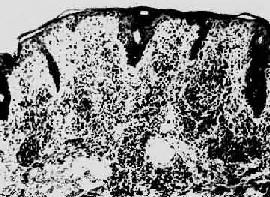

第二期梅毒第一期梅毒如不治疗,即使下疳愈合,潜伏于体内的螺旋体仍能继续繁殖,在感染后第8~10周左右大量进入血循环,引起全身广泛性皮肤粘膜病变,即梅毒疹(syphilid)。通常表现为口腔粘膜红斑丘疹、躯干、四肢、掌心和足心的斑疹、丘疹和口唇、外阴、肛周的扁平湿疣(condyloma lata)。后者表现为暗红色突起的平坦斑块。所有梅毒疹的组织学变化皆为淋巴细胞和浆细胞浸润构成的非特异性炎及闭塞性血管内膜炎和血管周围炎(图18-26),扁平湿疣则尚有表皮增生和角化不全。凡梅毒疹病灶内皆有苍白螺旋体。第二期梅毒有全身性淋巴结肿大,镜下为非特异性炎。少数患者可发生亚急性脑膜炎虹膜炎肝炎,以及免疫复合物反应所引起的膜性肾小球肾炎。梅毒疹也可不治“自愈”,但患者实际陷入隐性梅毒阶段,若不治疗,多年后30%的患者将发生第三期或晚期梅毒。第二期梅毒若予治疗,将阻止其向第三期梅毒发展。

梅毒疹

图18-26 梅毒疹

真皮呈致密的淋巴细胞及浆细胞浸润(采自Muir)